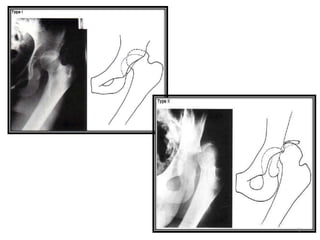

Tipo I: DISLOCACION

SUPERIOR

Fractura

asociada o

impactacio

n de

cabeza de

femur

asociada al

acetábulo

Luxación púbica y subespinosa

Sin fracturas asociadas

Tipo II: DISLOCACION

INFERIOR

Sin fracturas

asociadas

impactacion de

la cabeza del

Luxación obturatriz y perineal